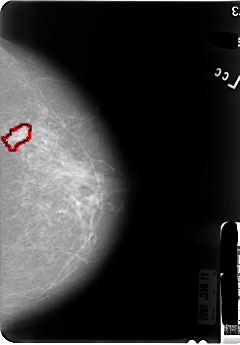

B_3046_1.RIGHT_MLO

FILE: B_3046_1.LEFT_MLO.OVERLAY

TOTAL_ABNORMALITIES 1

ABNORMALITY 1

LESION_TYPE MASS SHAPE IRREGULAR MARGINS SPICULATED

ASSESSMENT 4

SUBTLETY 3

PATHOLOGY MALIGNANT

TOTAL_OUTLINES 1

BOUNDARY